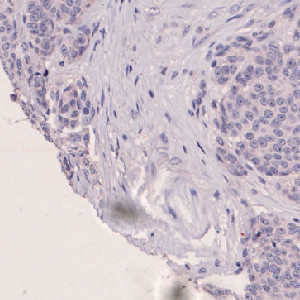

Nuclei surrounded by NT negative and weak NT positive.

Figure 4

Nuclei classified as negative (blue) or 1+ (yellow) based on the NT staining of each nucleus’ surroundings.